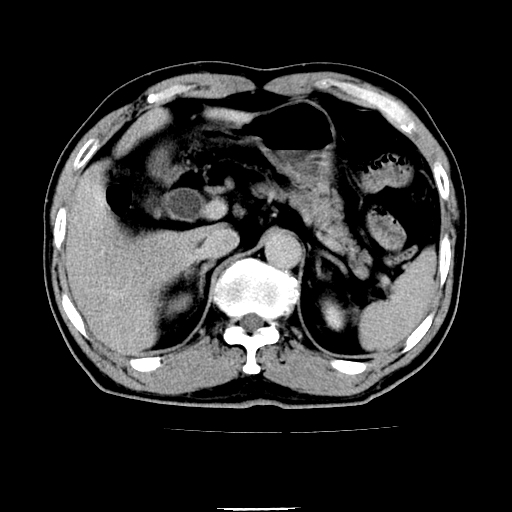

以下是引用chenqiong在2010-3-25 20:56:00的发言:[br]1、胆囊炎,胆囊息肉[br]2、肝内胆管及胆总管扩张,胆总管下端结石[br]3、十二指肠乳头旁憩室

以下是引用zxl51642在2010-3-26 10:47:00的发言:[br]胆囊炎,胆囊息肉,胆总管扩张,但未看到明显肿块,肝内胆管扩张不像恶性,炎性狭窄或阴性结石可能吧,建议mrcp,右肾小囊肿